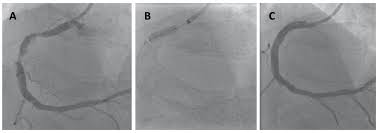

Η επέμβαση πραγματοποιείται με ακτινοσκοπική καθοδήγηση και στοχεύει στην αποκατάσταση της ροής αίματος σε στενά ή αποφραγμένα στεφανιαία αγγεία. Η προσπέλαση γίνεται συνήθως μέσω της κερκιδικής ή, εναλλακτικά, της μηριαίας αρτηρίας.

Ένας καθετήρας καθοδήγησης εισάγεται εντός της αορτής και τοποθετείται στο στόμιο της πάσχουσας στεφανιαίας αρτηρίας. Από εκεί, προωθείται ένας εύκαμπτος οδηγός σύρματος που διαπερνά τη στένωση και επιτρέπει την ασφαλή προώθηση του μπαλονιού και του stent.

Η αγγειοπλαστική πραγματοποιείται με διάταση του μπαλονιού στο σημείο της βλάβης, ενώ η τοποθέτηση του stent διατηρεί το αγγείο ανοικτό, μειώνοντας την πιθανότητα επαναστένωσης. Η επιλογή των υλικών βασίζεται στη μορφολογία της βλάβης, η οποία μπορεί να εκτιμηθεί με τη χρήση ενδοστεφανιαίας απεικόνισης ή φυσιολογικών μετρήσεων.